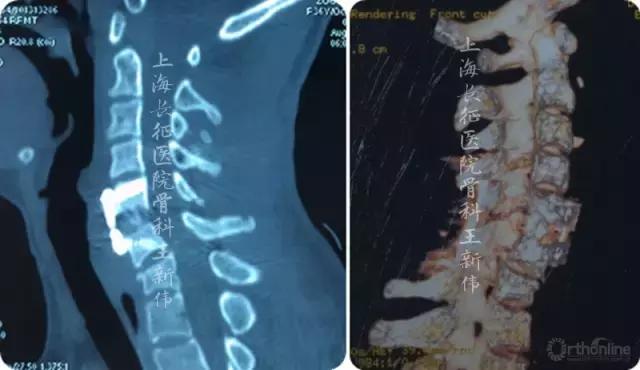

第一次术后影像学检查 :

第一次术后颈椎X线片

第一次术后颈椎CT三维重建,可见C6/7双侧仍存在关节绞锁